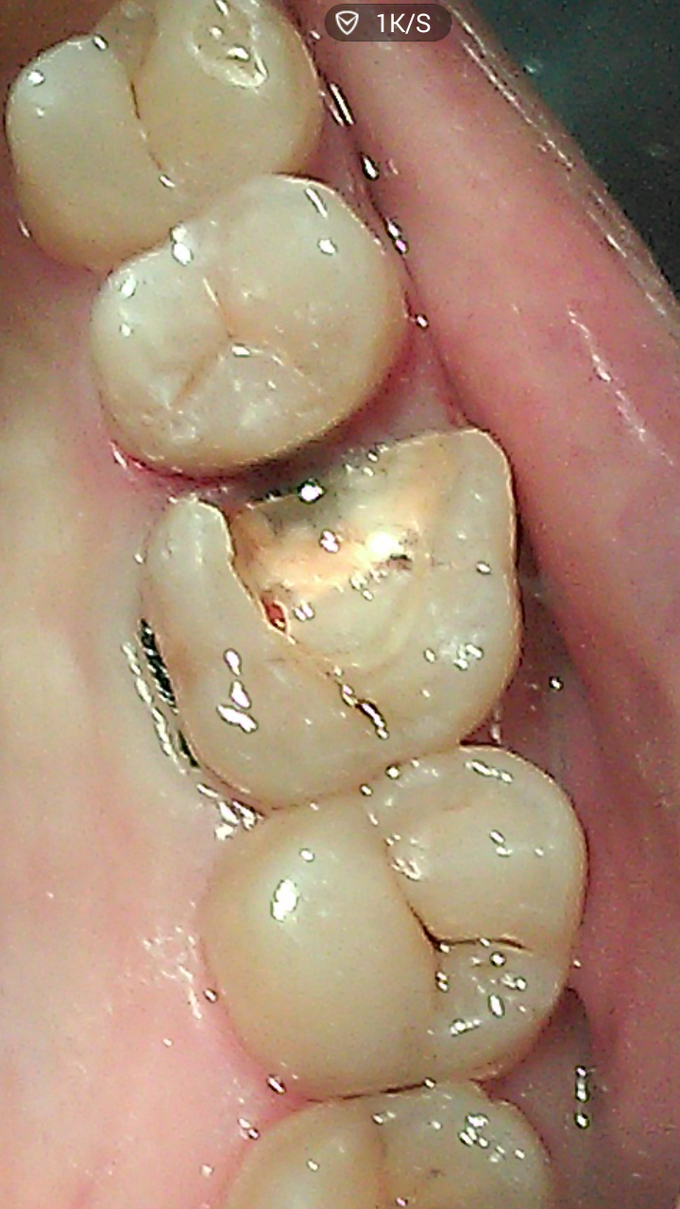

主诉:要求补牙。 病史:女,31岁。右上后牙大牙几年前在外院已做“根管治疗”,当时医生建议做冠,没同意。一直无不适,近日原充填物脱落,进食后易塞食物,要求重补。特别强调,还是不要做冠,不想磨牙太多。

查:16残冠,玻璃粘固粉充填,近中部分脱落,邻接关系不良,有食物嵌入,近中龈乳头轻度压迫性萎缩,轻度充血、红肿。根尖片示根管治疗质量可,根尖区无异常。咬合关系检查,16颊侧微倾,颊侧倒凹较大,颈部有楔缺,部分牙龈萎缩。

根据检查结果,提示,如冠修复,势必磨牙组织太多,更可怕的是,几乎全部釉质等坚硬组织可能去掉,这样基牙的抗力大大削弱。同时依据患者的要求,决定选用瓷嵌体修复。铸瓷价格偏高,病患没选择。 处理步骤: 1,牙周软组织准备,这一定要放在首位。去除结石,控制炎症。特别是判断生物学高度。避免后期的并发症。 2,硬组织准备:去尽腐质,薄壁弱尖,无基釉等。 3,寻找固位形,根管内,箱状等。 4,龈壁处理,这是最关键的部位,必要时使用“深部边缘提升”(Deep Margin Elevation,DME)。 5,垫底,填倒凹,结合流体树脂和通用树脂。 6,比色。本病例,因原牙体组织微发暗,色调不是太理想。 7,取精密印模。 7,试戴和粘固。